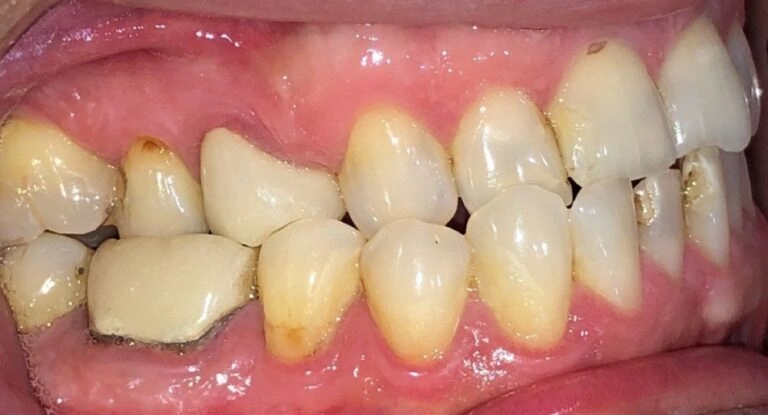

Why should you worry? If a deep bite goes unaddressed, the teeth don’t meet properly. This misalignment can cause severe wear and tear on the teeth over time, eventually leading to tooth breakage and even tooth loss. I’ve treated many adults who came in with worn-down teeth due to untreated deep bites.

Here’s a visual example of what this looks like:

Patient Example #1: Notice how the teeth are significantly worn down and chipped due to long-term misalignment.

Patient Example #2: A more severe case where untreated deep bites led to significant tooth wear and difficulty chewing.